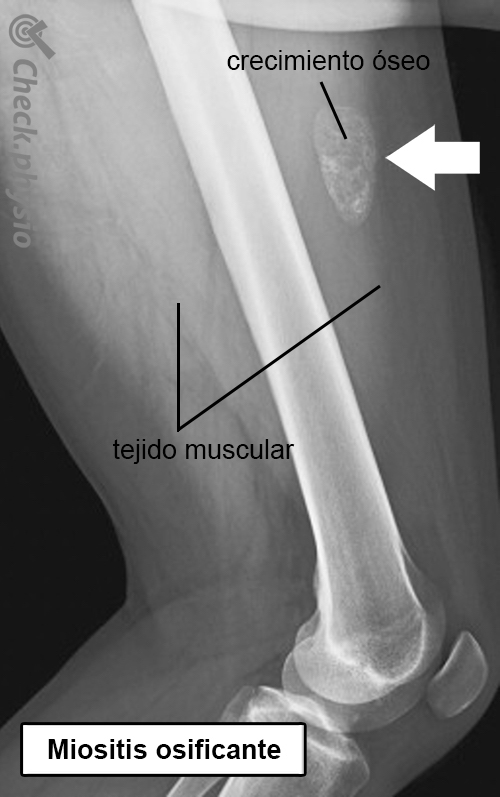

Miositis osificante Crecimiento óseo en un músculo

Cuando se forma hueso en un músculo, se habla de miositis osificante. Suele ser el resultado de una contusión muscular en la que un hematoma se convierte en tejido óseo. Un hematoma grande, tras una contusión muscular, puede provocar una miositis osificante en un 10 a 20 % de los casos.

La miositis osificante es un trastorno en el que una contusión muscular provoca la formación local de tejido óseo en dicho músculo. Tras sufrir una contusión (grave), se desarrolla un hematoma en el músculo. El organismo responde iniciando una reacción inflamatoria en el músculo (miositis). Esto puede causar calor, enrojecimiento, dolor e hinchazón. Esta reacción inflamatoria asegura el inicio del proceso de recuperación y la eliminación del hematoma. La mayoría de las veces, esto ocurre bastante rápido y las molestias se disipan en pocas semanas. Pero éste no es el caso con la miositis osificante, aquí. el hematoma se calcifica y forma un pequeño trozo de hueso. Este proceso se denomina osificación.

El médico o fisioterapeuta le preguntará acerca de este problema. En el caso de la miositis osificante, los síntomas suelen aparecer tras una contusión muscular que no mejora en dos semanas. Durante la exploración física, se puede palpar un bulto duro y doloroso en el músculo y la movilidad de la(s) articulación(es) por donde discurre el músculo está reducida. En una fase temprana, una radiografía no muestra anomalías, pero el trastorno se hace visible al cabo de tres o cuatro semanas. Una ecografía sí muestra el trastorno en una fase algo más temprana.